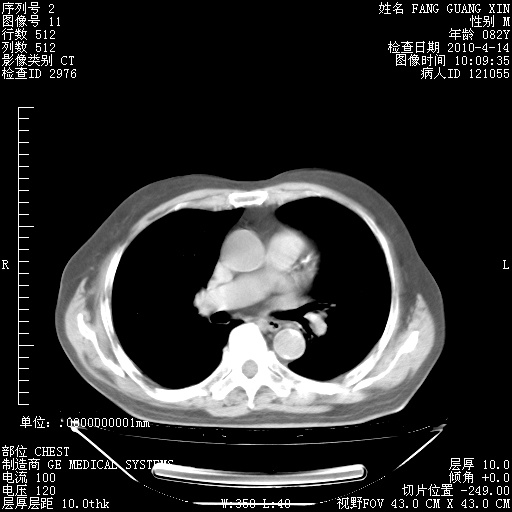

4月28日肺部CT——再次出现类似去年5月9日——透光度降低,(影像科认为)“间质性”改变。

4月28日肺部CT——再次出现类似去年5月9日——透光度降低,“间质性”改变。